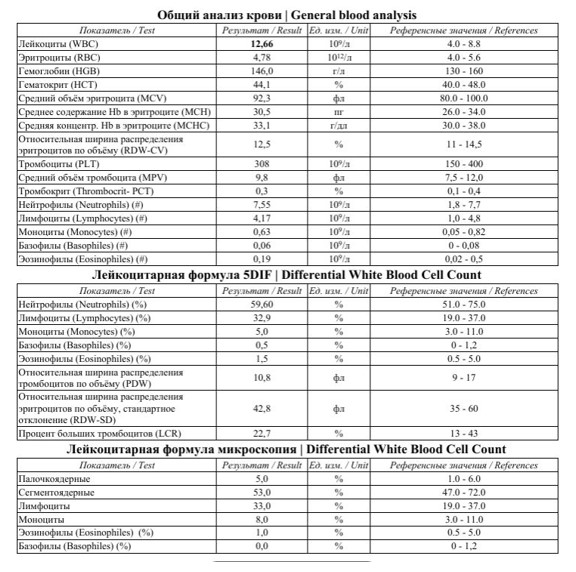

В биохимическом анализе крови при рецидивирующих наружных отитах обязательно стоит обращать внимание на показатели глюкозы крови, так как рецидивирующие воспалительные процессы часто являются симптомом Сахарного диабета. У данного пациента глюкоза крови в норме, но отмечается повышение СРБ, что также свидетельствует о наличии воспалительного процесса в организме:

При повторных анализах крови в результате лечения (через 10 дней) отмечается нормализация показателей Общего анализа крови и СРБ, что свидетельствует о выздоровлении.